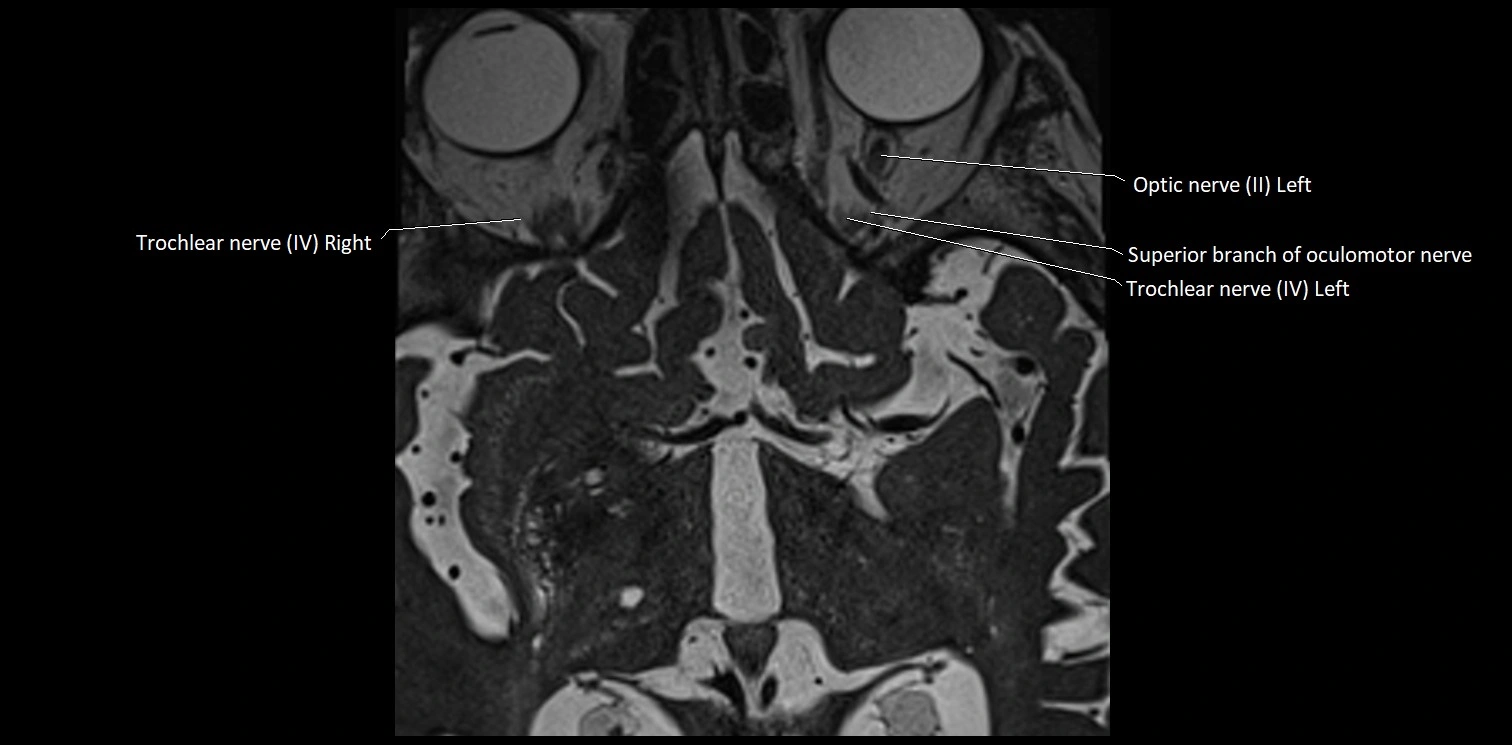

MRI Appearance

• The abducens nerve is a small, thin, linear structure

• Best visualized on high-resolution T2-weighted 3D MRI sequences (e.g., FIESTA or CISS)

• Seen as a hypointense (dark) line running from the brainstem at the pontomedullary junction, traversing the prepontine cistern, and entering Dorello’s canal under the petrosphenoidal ligament, then into the cavernous sinus, and finally the orbit

• May be challenging to visualize in standard MRI due to its small size

• Pathology may be inferred by absence, displacement, or enhancement of the nerve

MRI images

image